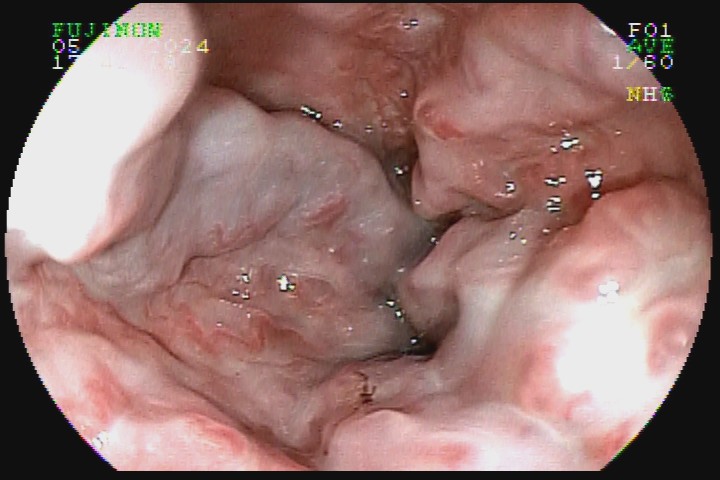

As varizes esofágicas devem ser classificadas em pequeno (<5mm), ou grosso calibre (>5mm), sendo esse o principal marcador prognóstico para o risco de sangramento e definição de conduta.

A presença de sinais da cor vermelha também é importante fator prognóstico. Eles surgem na superfície das varizes e são decorrentes da dilatação das vênulas superficiais, podendo ser em forma de vergão (red weal mark), de manchas cerejas (red spots) ou mancha hematocística.